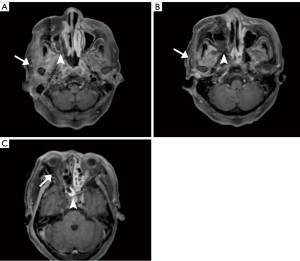

After admission, laboratory tests indicated random blood glucose (GLU) level of 12.74 mmol/L (normal value ≤11.1 mmol/L), base excess (BE) level of −3.4 mmol/L (normal range, −3 to +3 mmol/L), β-hydroxybutyric acid (β-Hb) level of 3.61 mmol/L (normal range, 0.02–0.27 mmol/L), white blood cell count (WBC) level of 17.44×109/L (normal range, 3.69–9.16/L), procalcitonin (PCT) level of 0.46 ng/mL (normal range, 0.00–0.05 ng/mL) and interleukin-6 (IL-6) level of 317 pg/mL (normal range, 0.00–7.00 ng/mL). Considering the presence of infection and diabetic ketoacidosis, the patient was given symptomatic treatment such as hypoglycemic therapy, ketone body lowering measures, and empirical anti-infection. A head computed tomography (CT) scan revealed a cerebral infarction in the right parietal lobe (Figure 1A). On hospital day 7 (2023-09-02), the patient’s mental status deteriorated to shallow coma. Follow-up cranial CT demonstrated progression of the cerebral infarction with concomitant cerebral herniation (Figure 1B). Cerebrospinal fluid (CSF) analysis showed leukocytosis (326×106/L; normal: 0–8 ×106/L) and elevated microalbumin (86.1 mg/dL; normal: 8.0–43.0 mg/dL). Concurrent metagenomic next-generation sequencing (mNGS) of CSF detected Rhizopus oryzae (76 sequences), confirming intracranial mucormycosis. Fungal meningitis (Rhizopus oryzae) complicated by cerebral infarction was diagnosed based on clinical and ancillary findings. Emergency right frontotemporal-parietal debridement with dural repair and intracranial pressure transducer placement was performed that day. The patient maintained stable vital signs intraoperatively, and postoperative cranial CT was obtained (Figure 1C). By September 9, 2023, surveillance cranial CT (Figure 1D) showed unchanged right hemispheric infarction extent with normalized density and resolved cerebral edema. On the second day of admission (2023-08-28), contrast-enhanced cranial MRI (Figure 2) demonstrated multiple right hemispheric infarcts. Contrast-enhanced orbital MRI (Figure 3) revealed soft tissue swelling in the right maxillofacial region and bilateral periorbital areas. After enhanced scanning, prominent enhancement was noted, suggesting infectious lesions and multiple groups of sinusitis. At the same time, CSF mNGS confirmed Rhizopus oryzae infection (as above). After identification of the pathogenic bacteria, liposomal amphotericin B (L-AMB) and posaconazole suspension were administered for antifungal treatment. Additionally, serial monitoring of infection markers—including complete blood count, PCT, and IL-6—showed progressive improvement (Figures 4,5).

In this case, the patient’s initial symptom was a periorbital skin infection, which subsequently manifested as symptoms of orbit apex syndrome. With further imaging, it revealed multiple infarct foci in the right cerebral hemisphere. According to the facts that the existence of the patient’s diabetes mellitus and risk factors for cerebral infarction, primary cerebral infarction could not be ruled out. In combination with the patient’s past medical history of facial infections and diabetes mellitus, the patient’s relevant pathogenetic examinations including NGS were performed on the second day of admission. Additionally, the presence of Rhizopus oryzae infection was shown on the return of the mNGS of the CSF sent for examination, which was ultimately considered to be a cerebral infarction secondary to a fungal infection, namely ROCM. Non-enhancing hypointense mucosa (“black turbinate sign”) observed on contrast-enhanced MRI in this case reflects microthrombosis and mucosal necrosis caused by vascular invasion of Mucorales. This imaging feature is highly consistent with histopathological ischemic necrosis and serves as an early warning marker for acute invasive fungal sinusitis (9). Notably, although mucosal thickening may also occur in ordinary sinusitis, its enhancement pattern is typically homogeneous, whereas the focal non-enhancement areas associated with the BT sign represent a key distinguishing feature. Subsequently, antifungal therapy was promptly initiated and surgery was performed to treat the intracranial lesion, achieving good effectiveness.